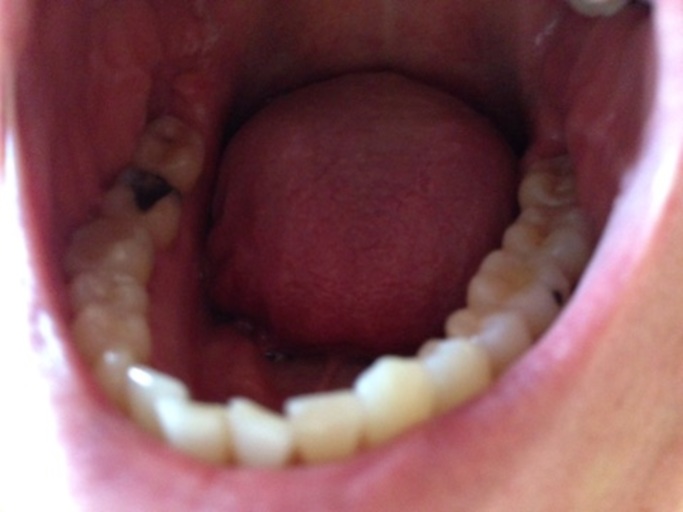

Small Cavity in the Lower Right Molar

Hi there, I am Zaldi and a student at Boise State University, I have a small cavity on the lower right molar tooth, - I want to know how much a filling or cavity treatment is for this case, and - I want to ask if there is any schedule that I can fit into this month so I can set up an appointment with you guys if that is possible. Best, Zaldi